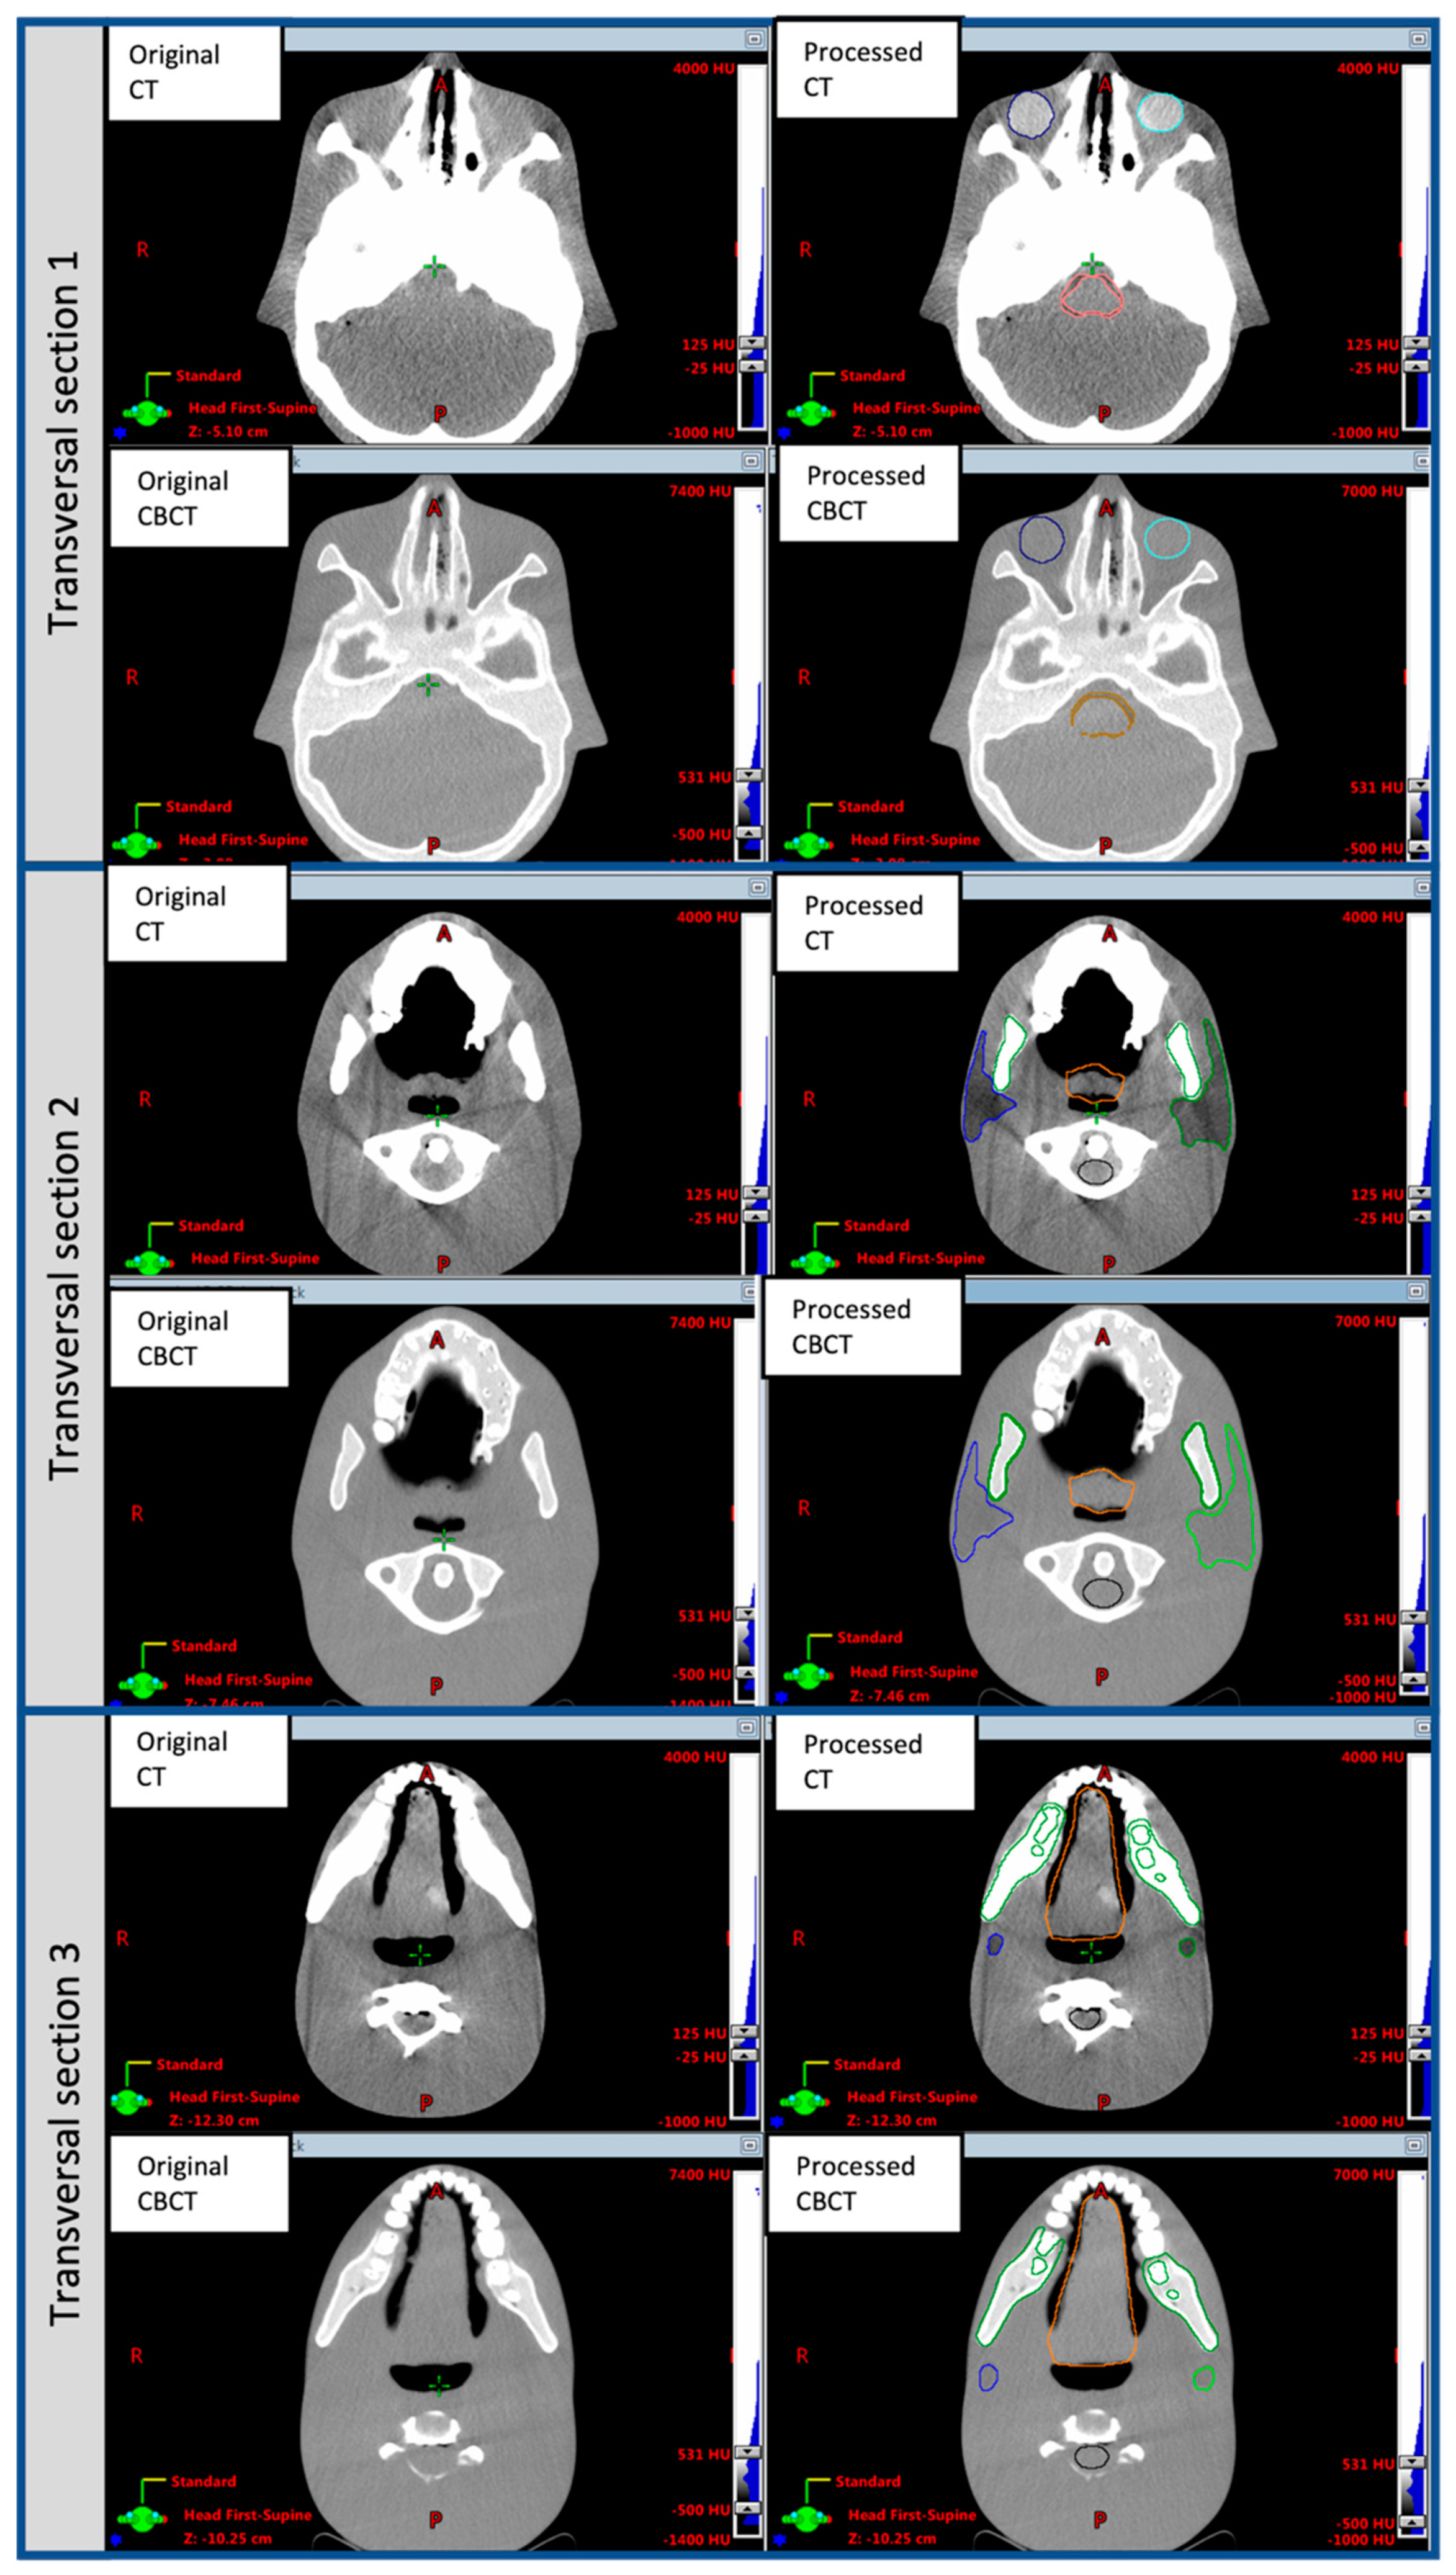

The original and post-processed CT and CBCT phantom images in three different transverse sections are shown in Figure 2. Table 1 reports the HU values of OARs in the original and processed CT and CBCT phantom images. Both post-processed phantom image sets have been made publicly available as additional downloadable material for this paper, as Supplementary Material.

Figure 2.

Original and post-processed CT and CBCT transverse sections of the CIRS ATOM Max Dental and Diagnostic Head Phantom Model-711 used in the method presented for DIR accuracy evaluation. Sections were chosen to visualize organs of interest. The HU values of parotid glands, larynx, oral cavity, brainstem and eyes were digitally modified using MATLAB and CERR tools, as described in Section 2.1.